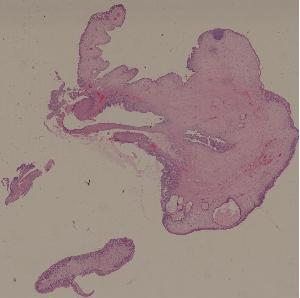

28. Adenoma of the colon